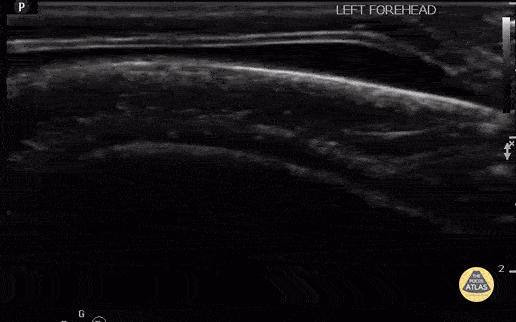

8 month old with scalp hematoma, no underlying skull fracture. The hematoma is denoted by the hypoechoic protuberance, superficial to the hyperechoic bone. Contributor: Antonio Riera, MD